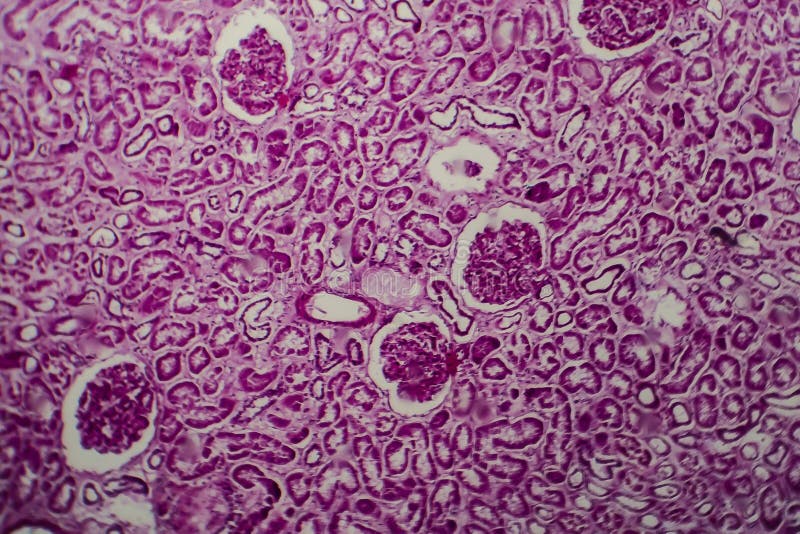

Acute Diffuse Proliferative Nephritis Inflammation

Hyperemia, edema and inflammatory infiltration in interstitial tissue 56. A number of distinct agents can cause apgn but the pathogenesis of all appears to involve generation of circulating immune complexes.